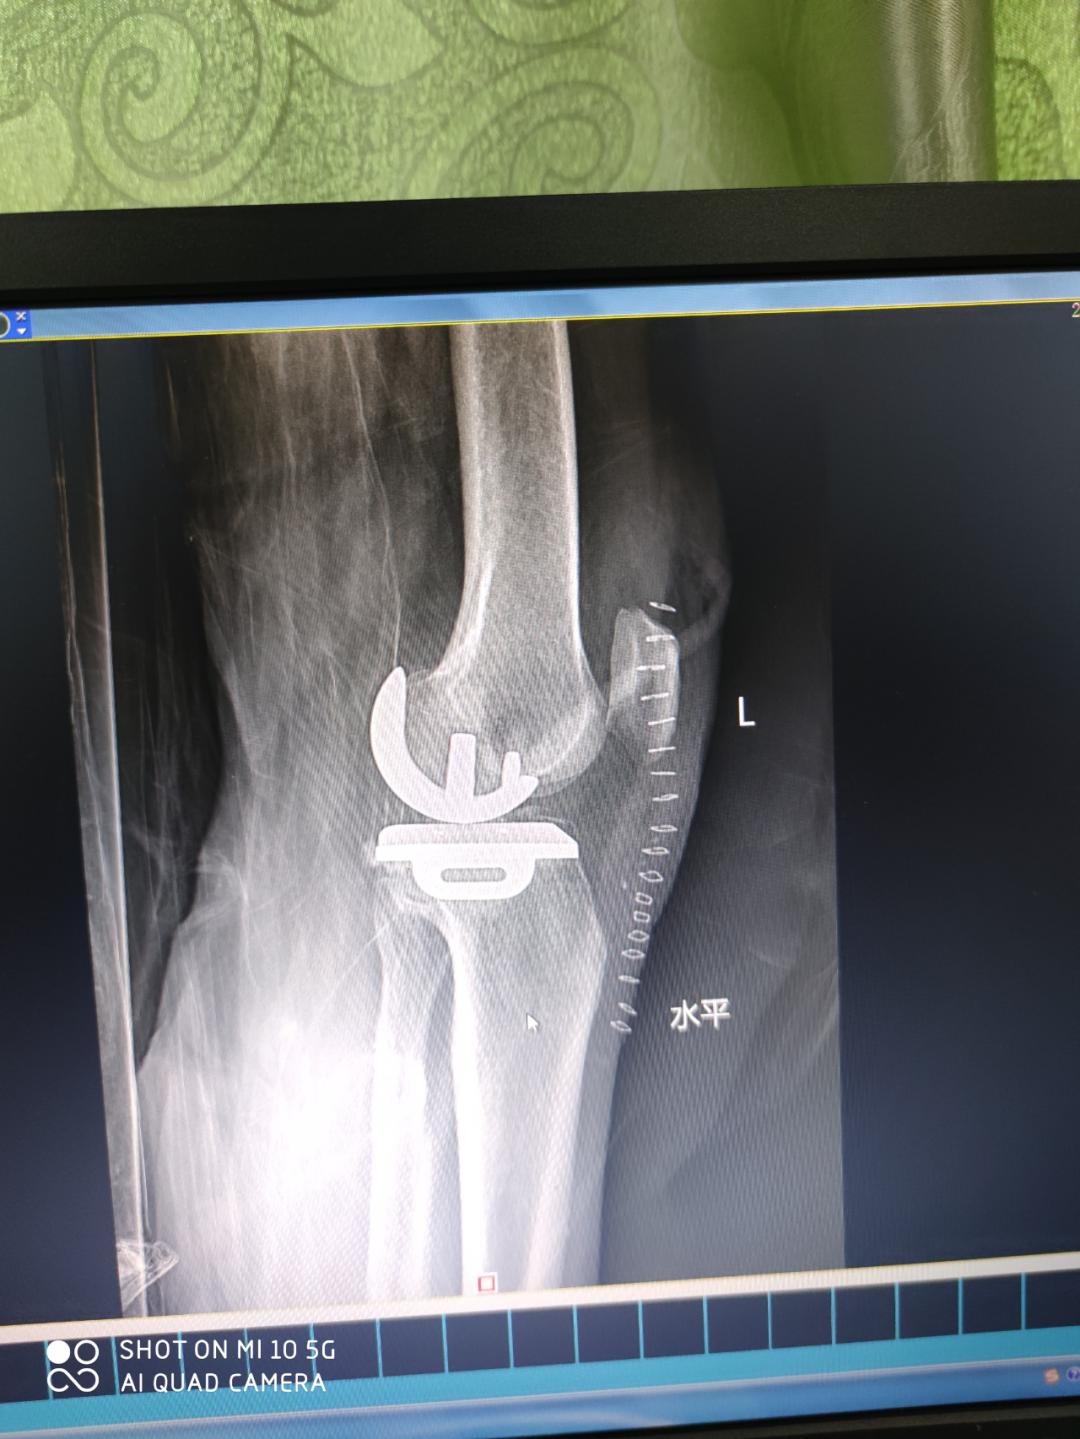

术中

关节外科主任医师农家隆介绍,UKA技术在国内各大型医院已成为治疗膝关节骨关节炎的新型术式,具有损伤小、出血少、恢复快、住院时间短等特点,术后患者可以得到较好的活动度,以及接近正常的本体感觉,所以为众多关节外科专家和患者所接受。